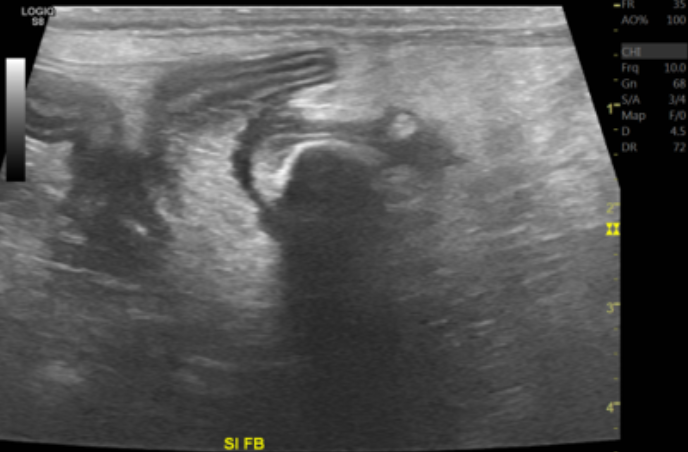

추가로 진행한 초음파 검사에서 위와 십이지장 안에 가스가 차 있었으며, 소장 안에는 둥근 형태의 이물과 실 모양의 이물 음영이 관찰되었습니다.

그 주변으로 복막에 심한 염증과 소량의 복수가 함께 확인되었습니다.

이물로 인해 장이 완전히 막힌 상태로 보이진 않았지만, 장벽의 부종과 염증, 일부 누출 소견이 있어 탐색적 개복 수술을 진행하기로 했습니다.